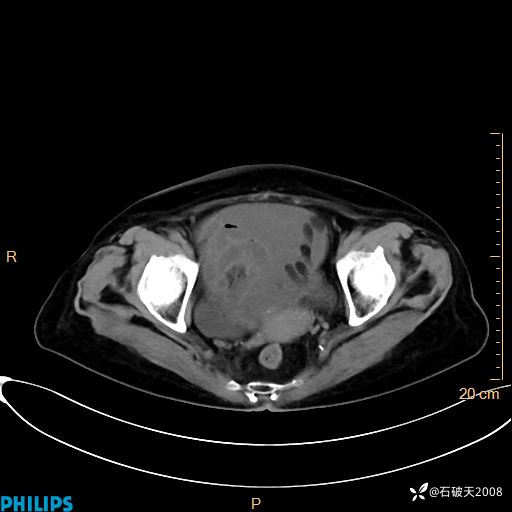

动脉期